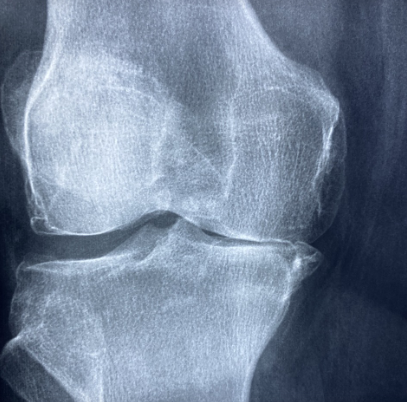

연골연화증의 진단은 비교적 간단하지만 정확한 상태 파악을 위해 여러 방법이 활용됩니다. 우선 의사의 문진과 신체 검진을 통해 무릎 주변 압통, 통증 유발 자세 등을 확인합니다. 이후 X-ray로 뼈 상태를 체크하고, MRI를 통해 연골의 연화 정도나 손상 범위를 정밀하게 평가합니다. MRI는 비침습적이고 정확도가 높아 연골 상태를 직접적으로 관찰할 수 있어 가장 선호되는 진단법입니다. 경우에 따라 관절 내시경으로 무릎 안을 직접 들여다보며 연골 손상 여부를 확인하기도 합니다. 조기 진단이 예후에 큰 영향을 미치므로 증상이 의심될 경우 병원을 찾는 것이 중요합니다.